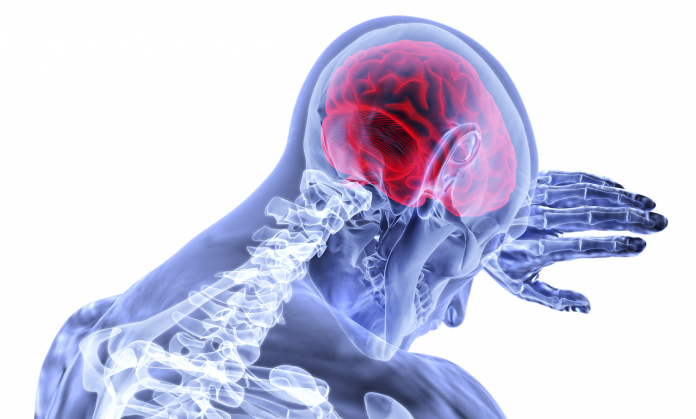

Se podrían aplicar medidas de prevención del contagio de COVID-19 que ha tenido serios efectos en el sistema nervioso central como dolor de cabeza

De acuerdo con un estudio publicado este lunes en la revista científica Nature Neuroscience, el COVID-19 podría llegar hasta el cerebro si entra a través de la nariz lo que explicaría varios de los síntomas neurológicos.

Incluso, con ello también se podrían aplicar medidas de prevención del contagio que ha tenido serios efectos en el sistema nervioso central lo que ha resultado en dolor de cabeza, fatiga y náuseas.

De hecho, los síntomas neurológicos más comunes son la pérdida del olfato y del gusto, ya que los estudios recientes también muestran la presencia de ARN del virus en el cerebro y en el líquido cefalorraquídeo.